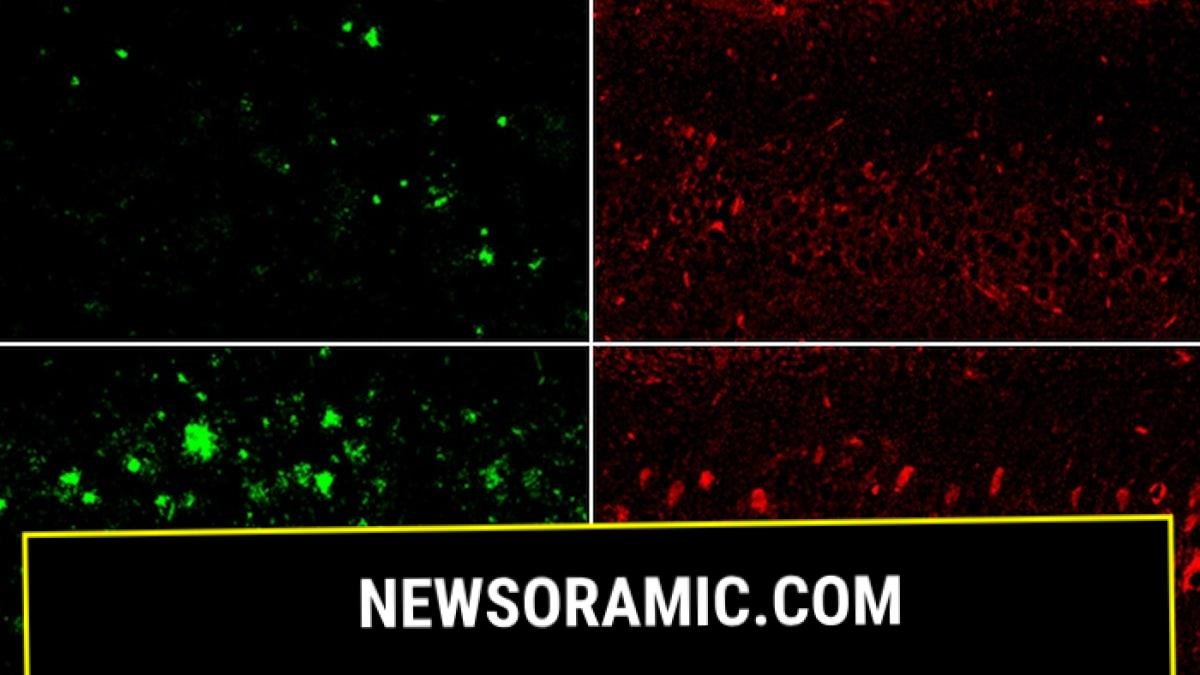

Lithium deficiency thinned the myelin that coats neurons, right, compared to normal mice. (Yankner Lab)